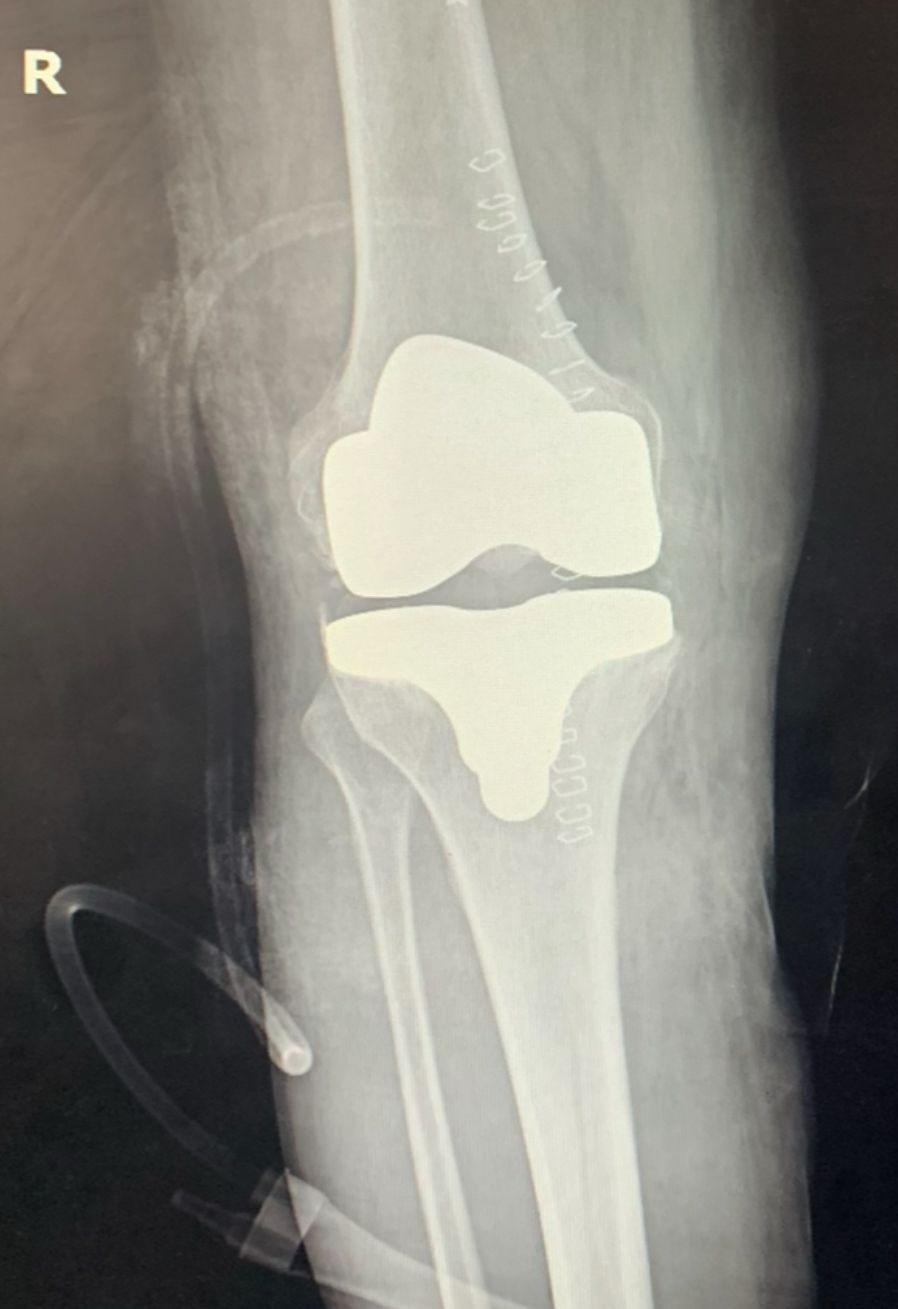

• Prótesis de rodilla

Fotos y videos